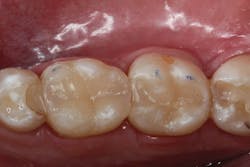

After both restorations were filled, the rubber dam was removed and the occlusal contacts were adjusted. The final polish of the restoration was achieved with a Jiffy abrasive polishing brush (Ultradent Products), which is a silicon carbide impregnated polishing brush. The high polish achieved by the Ecosite Bulk Fill composite can be credited to homogenously dispersed nanofillers (figure 10).

Figure 9: Favorable proximal contours achieved on the distal of tooth No. 30

Additionally, the translucency of the composite allows it to blend well with the surrounding tooth structure. The final restorations should have adequate bond and strength to withstand oral function, as well as sufficient polish and contour to give the patient the opportunity to maintain these restorations with proper hygiene.

Figure 10: The final polish and translucency of Ecosite Bulk-Fill composite